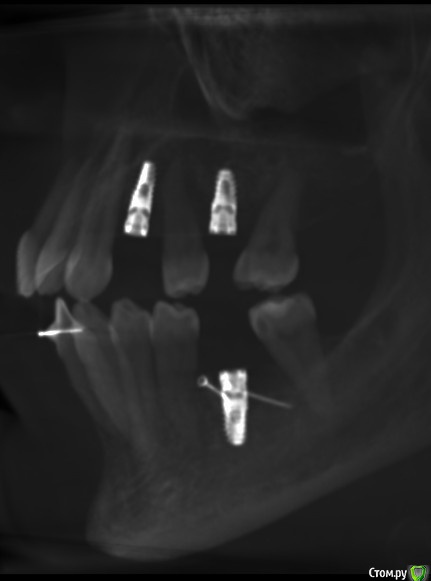

Делалась установка имплантов 5-6 месяцев назад. Скоро буду установлены формирователи десны, а потом временные коронки, с которыми ходить полгода. Для того, чтобы за это время свести к минимуму последующее обтачивание своих здоровых зубов при постановке постоянных коронок на импланты, ортопед отправил на консультацию к ортодонту, сказав, что можно попытаться если не полностью, то хотя бы с каким-то эффектом переместить сместившиеся зубы. Хирург в некотором роде поддержал, сказав, что использование временных коронок в качестве опоры для перемещения даст нагрузку на импланты и будет даже положительным фактором, если нагрузка не будет слишком большая.

Одна отнеслась к описанной ситуации совершенно спокойно, согласилась, что слишком большую нагрузку давать не надо, а потихоньку можно вполне успешно закрепить ортодонтическую конструкцию на временных коронках 24 и 26 для перемещения с помощью пружин зуба 25 к 24, а зуба 27 - от 26, туда, где они и были не так давно, перед имплантацией. По времени спрогнозировала порядка 3-4 месяцев. В отношении зуба 37 с отталкиванием от временной коронки на 36 тоже никаких возражений не было, только по времени могло быть немного дольше, так как кость плотнее.

Вторая категорически отвергла укрепление дуг брекетов на 24 и 26. Мотивировала это низкой плотностью кости на этом участке, при которой пострадают импланты. Сказала, что если перемещать конкретно два зуба 25 и 27, то она прикрепит конструкцию только к ним, и они будут отталкиваться друг от друга без участия временных коронок. Прогноз по сроку увеличился от 6 до 12 месяцев, причём ещё была озвучена вероятность выталкивания зуба 25 при перемещении в наружную сторону. По зубу 37 опора на временную коронку на импланте также была отвергнута и предложен вариант с перемещением при помощи вкрученного мини-импланта в кость за зубом.